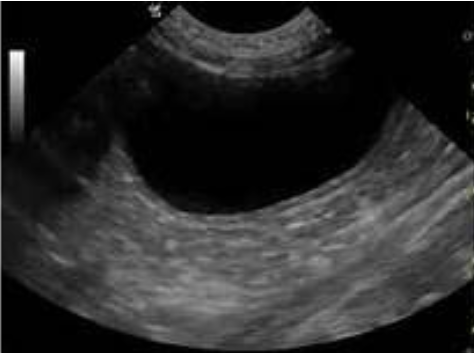

Urinary bladder

bladder wall should be smooth and uniform

routinely used to collect urine sample via cystocentesis

Function:

- collect, store, and release urine